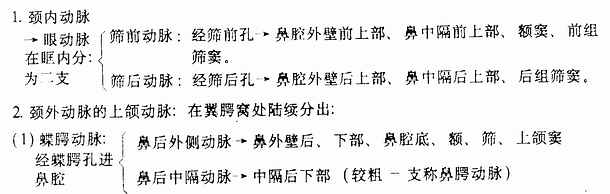

(一)动脉:主要来自颈内动脉的眼动脉(ophthalmic artery)及颈外动脉的上颌动脉(internal maxillary artery),其行径分布如下:

筛前动脉、筛后动脉中隔支、上唇动脉、腭大动脉、鼻腭动脉在鼻中隔前下部构成丰富的动脉丛为鼻出血的好发部位(图1-11)

图1-11 鼻中隔动脉分布